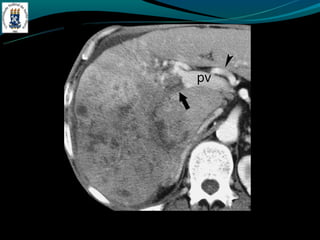

BUDD-CHIARI

- TC: hepatomegalia heterogênea, não visualização das veias

hepática, ascite, realce hepático central, lobo caudado preservado

ou aumentado.

BUDD-CHIARI -Hipercoagulabilidade -Compressão – tumor -Membranada VCI -Dor abdominal, hepatomegalia e ascite. - TC: hepatomegalia heterogênea, não visualização das veias hepática, ascite, realce hepático central, lobo caudado preservado ou aumentado.